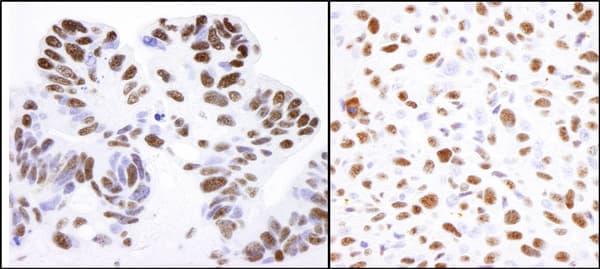

Rabbit Polyclonal Nucleolin antibody. Suitable for IHC-P, ICC/IF, IP, WB, ICC and reacts with Mouse, Human samples. Cited in 17 publications. Immunogen corresponding to Synthetic Peptide within Human NCL aa 550 to C-terminus.